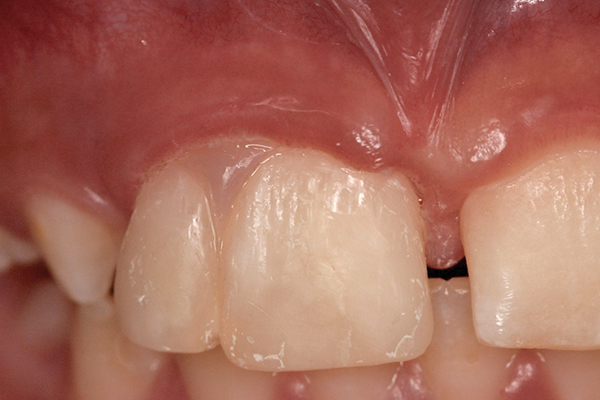

A 9-year-old girl, referred to a prosthodontic office by her pediatric dentist, presented with her mother’s chief complaint: “The kids are teasing her about her big front tooth.” Findings from radiographic and clinical examinations revealed fused maxillary central-peg lateral incisors, teeth Nos. 7 and 8, and a congenitally missing lateral incisor, tooth No. 10 (Figure 1 through Figure 3). An implant was selected as the ideal treatment to replace tooth No. 10 when somatic growth was complete. A diagnostic wax-up was fabricated to determine if the fused tooth could be made to resemble two teeth, using pink composite to give the illusion of an interproximal papilla. The patient was referred for an orthodontic consultation to plan for closure of the diastema between teeth Nos. 8 and 9 and achievement of proper alignment for implant No. 10. The patient was also referred to a periodontist for pretreatment assessment of the tooth No. 10 site. An endodontist was consulted should exposure of the large pulp occur during tooth preparation.

Fig 1 and Fig 2. Pretreatment photographs. Patient at 9 years of age on presentation.